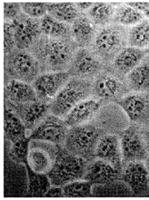

2.2 PS-ODN对801-D集落形成及细胞形态的影响 结果显示经5μmol/L PS-ODN处理,801-D集落形成率明显低于5μmol/L CPS-ODN组和空白对照组(P<0.01)。5μmol/L CPS-ODN组集落形成率与空白对照组比较无显著差异(P>0.05)。PS-ODN对801-D集落形成有很强的抑制作用,抑制率达89%(表2)。镜下观察显示,实验组细胞有明显的形态学改变,主要表现为每集落细胞数少,呈纤维细胞样改变,细胞扁平,表面较多纤维状突起。内部结构不清,胞浆少(图1)。

图1 PS-ODN对801-D细胞形态的影响

A:CPS-ODN(5μmol/L);B:PS-ODN(5μmol/L)

Fig 1 Influence of PS-ODN on morphology of 801-D cell lines